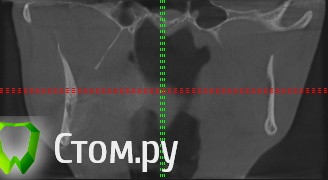

sergey765 Опубликовано 11 июня, 2014 Автор Поделиться Опубликовано 11 июня, 2014 посмотрите пожалуйста КТ. Ссылка на комментарий

sergey765 Опубликовано 11 июня, 2014 Автор Поделиться Опубликовано 11 июня, 2014 могу вам ещё снимков выложить.их довига. беспокаят меня боли после удаления .прошло 5 недель. снимки девушка лет 20 эти смотрела. сказала что у меня там инфекции дофига. типа давай я тебя на понедельник к хирургу запишу. он ранку вскроет. прочистит Ссылка на комментарий

Bier Опубликовано 11 июня, 2014 Поделиться Опубликовано 11 июня, 2014 это все не информативные кадры, в прикрепленных темах есть инструкция, выкладывайте КТ целиком, наш рентгенолог скачает и выложит срезы. 3 Ссылка на комментарий